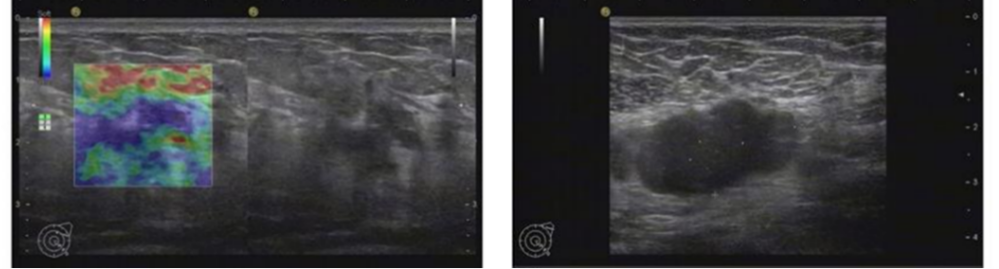

2021年6月颅脑增强MRI:左侧小脑占位,考虑转移瘤。

图2.颅脑增强MRI